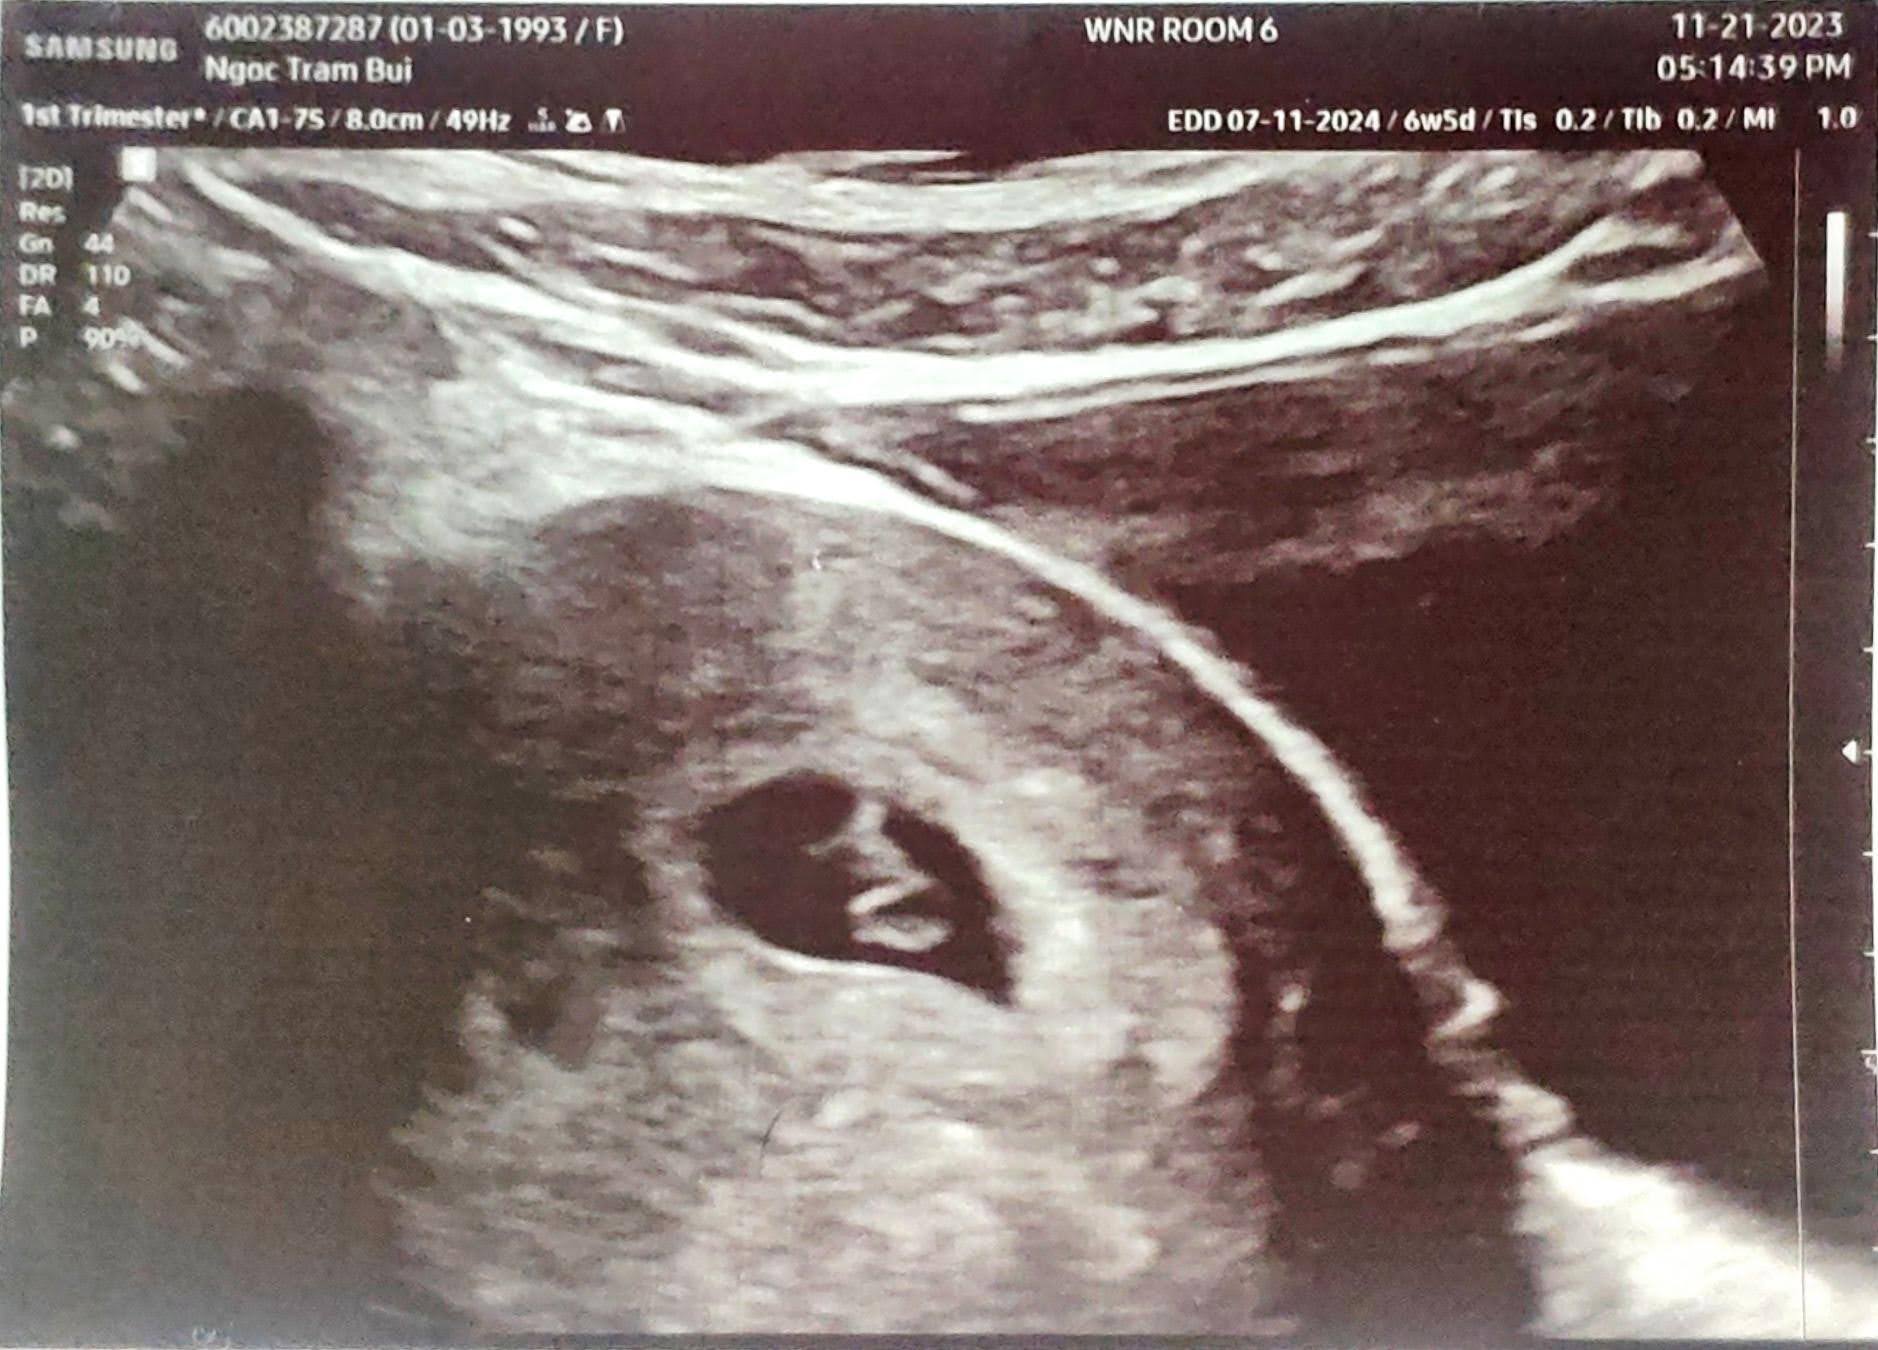

Đi ultrasound

7 Nov 2023

Một ngày mà hoàn tất xét nghiệm máu và siêu âm. Niềm vui khôn xiết vì đã thấy được tim thai